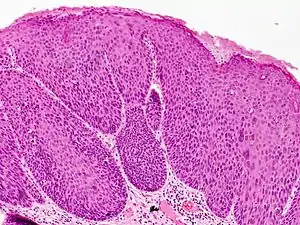

Bowenoid papulosis

Bowenoid papulosis is a cutaneous condition characterized by the presence of pigmented verrucous papules on the body of the penis.[1]:730[2]:408 They are associated with human papillomavirus, the causative agent of genital warts.[3] The lesions have a typical dysplastic histology and are generally considered benign, although a small percentage will develop malignant characteristics.